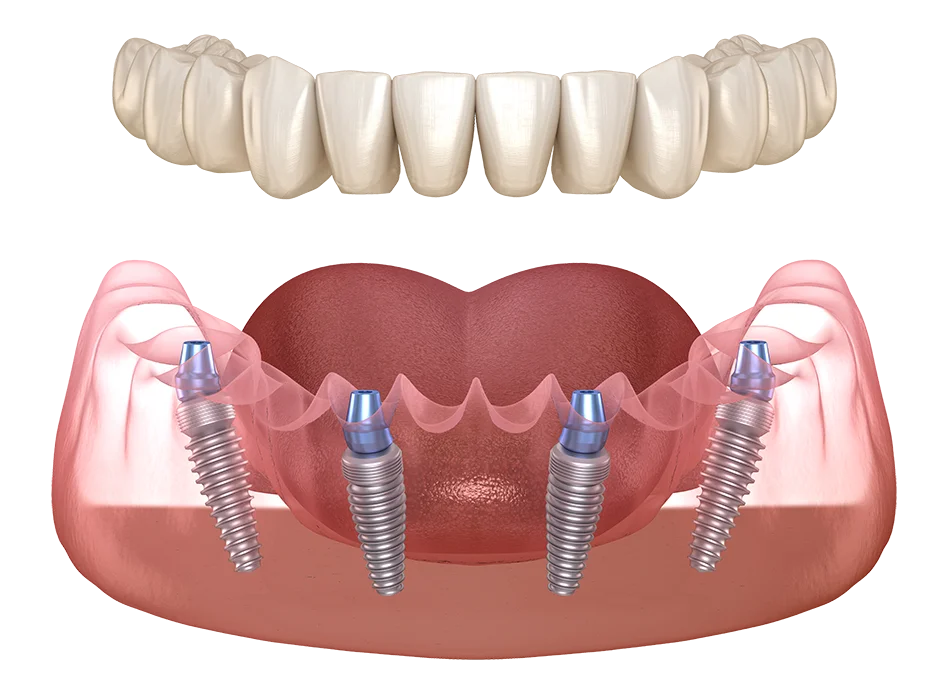

In cele mai multe cazuri, solutia pentru cea mai buna proteza dentara totala este reprezentata evident de o proteza dentara totala fixa pe 4 sau 6 implanturi, de care pacientii se pot bucura pret de o viata intreaga, realizata prin metoda dinti ficsi All-on-X.

Cate implanturi sunt necesare pentru fixarea unei proteze dentare?

Pentru a obtine o dantura totala fixa pe implanturi, de regula, se utilizeaza o proteza fixa cu 6 implanturi la maxilar (All-on-6) si o proteza fixa cu 4 implanturi la mandibula (All-on-4).